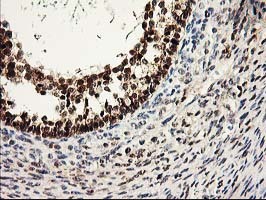

- Immunohistochemical staining of paraffin-embedded Human endometrium tissue within the normal limits using anti-PRMT2 mouse monoclonal antibody. (Heat-induced epitope retrieval by 10mM citric buffer, pH6.0, 100C for 10min, TA503643)